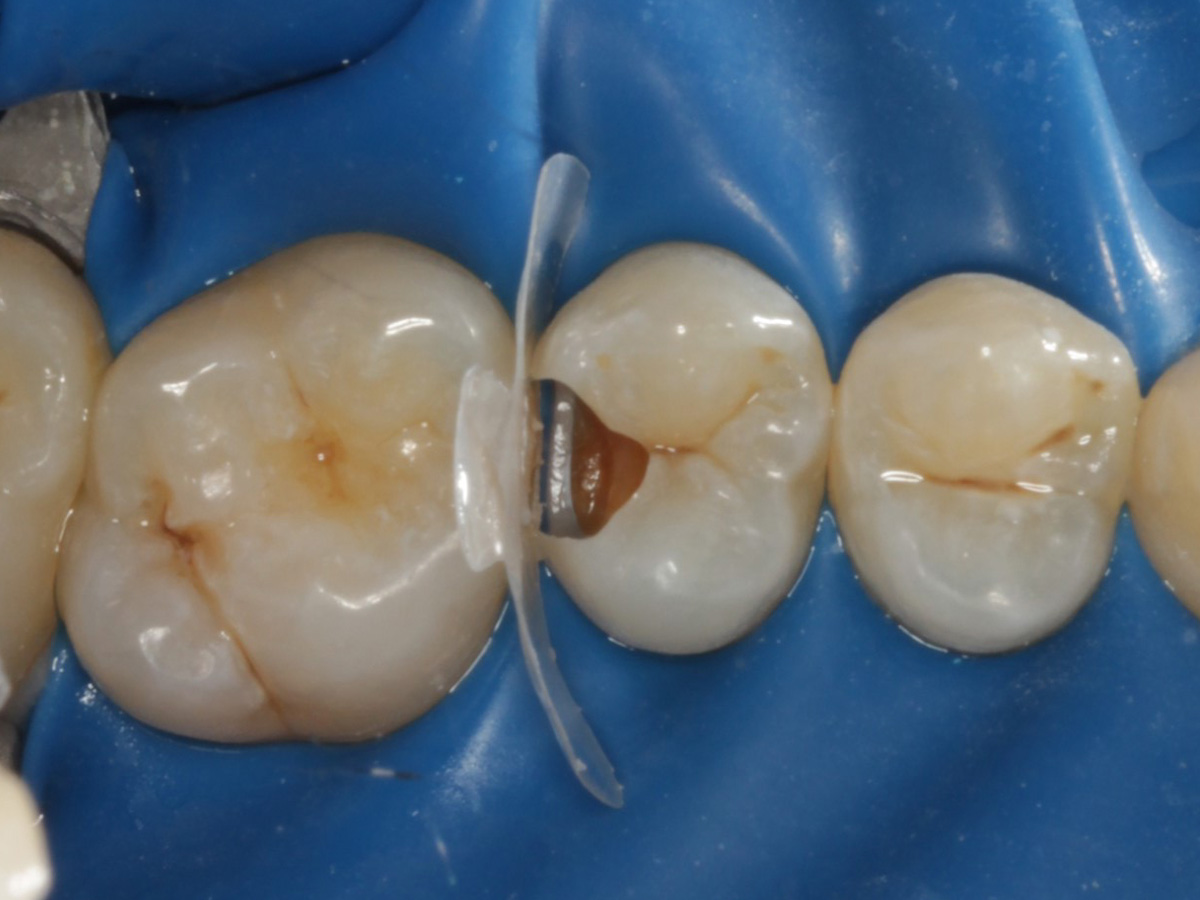

Abbildung 12

Nach erneuter Applikation des Einkomponentenadhäsivs und tief approximal eines fließfähigen Bulkkomposits, der Lichthärtung, und der Applikation des Bioclear Diamond Wedges Medium

Abbildung 13

Weiteres Flowkomposit appliziert und Bioclear Twin Ring Universal angebracht